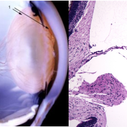

Vascular Primary Vitreous

The hyaloid artery (“3”, left) feeds the vasa hyaloidea propria (“2”, left) which anastomosis with the tunica vasculosa lentis (“1”, left). The histologic section to the right is stained with H & E (bar = 100 uM) [Left: from Yee at al.: Vitreous cytokines and regression of the fetal hyaloid vasculature. In: Vitreous – in Health & Disease. Springer, New York, 2014; pg. 42 (image © Springer Nature, reprinted with permission) Right: from Sebag J: Vitreous and vitreo-retinal interface. In: Ryan’s Retina 6th edition (A. Schachat, ed.) Elsevier, 2018; pg. 546.

Condition/keywords: hyaloid artery, vitreous